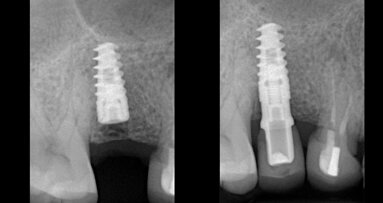

Náhrada PMMA je provizorium, které slouží k testování dosedů, anatomie a upřesňuje okluzní vztahy – štoly nejsou angulované. Na zubu číslo 23 je vidět otvor v incizní oblasti a je vizualizován budoucí otvor definitivní náhrady.

Návrh definitivní náhrady: angulace vyřešila problém narušení incizální hrany zubu 23

Při výrobě náhrad v laboratoři je požadavek na maximální estetiku občas v rozporu s technickými možnostmi danými osou zavedení implantátů. Nutí nás tak ke kompromisům jako jsou cementované náhrady, kde ohrožujeme náhradu nekontrolovaně zatečeným cementem. Osa implantace nás také často nutí nevyrábět náhrady šroubované, avšak nový systém Dynamic Dental nám umožnuje si „vyhrát“ s umístěním otvoru pro šroubek mimo estetickou oblast a vytvořit skutečně vysoce anatomické a estetické náhrady.